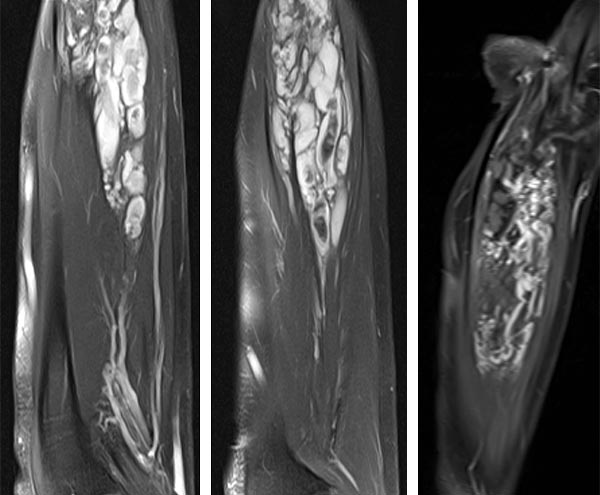

MRT-Bildgebung des Unterarms in T2-Wichtung mit spektraler Fettsättigung nach Gadoliniumgabe (links, Mitte). Es zeigen sich die charakteristisch dilatierten venösen Konvolute, die in der Spätphase mit Kontrastmittel anreichern (rechts). Die zentralen Thrombosierungen kommen innerhalb dieser Kavernen als schwarze Aussparungen zur Darstellung.